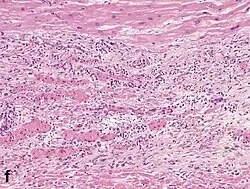

Although earlier changes can be discerned using electron microscopy, one of the earliest changes under a normal microscope are so-called wavy fibers.[23] Subsequently, the myocyte cytoplasm becomes more eosinophilic (pink) and the cells lose their transversal striations, with typical changes and eventually loss of the cell nucleus.[24] The interstitium at the margin of the infarcted area is initially infiltrated with neutrophils, then with lymphocytes and macrophages, who phagocytose ("eat") the myocyte debris. The necrotic area is surrounded and progressively invaded by granulation tissue, which will replace the infarct with a fibrous (collagenous) scar (which are typical steps in wound healing). The interstitial space (the space between cells outside of blood vessels) may be infiltrated with red blood cells.[22]

| Neutrophil infiltration | 12–24 h | 1–3 days | 5–7 days |

| Karyorrhexis of neutrophils | 1.5–2 days | 3–5 days |

| Macrophages and lymphocytes | 3–5 days | 5–10 days (including 'siderophages') | 10 days to 2 months |

| Fibroblast and young collagen* | 5–10 days | 2–4 weeks | After 4 weeks; depends on size of infarction; |

| Dense fibrosis | 4 weeks | 2–3 months | No |